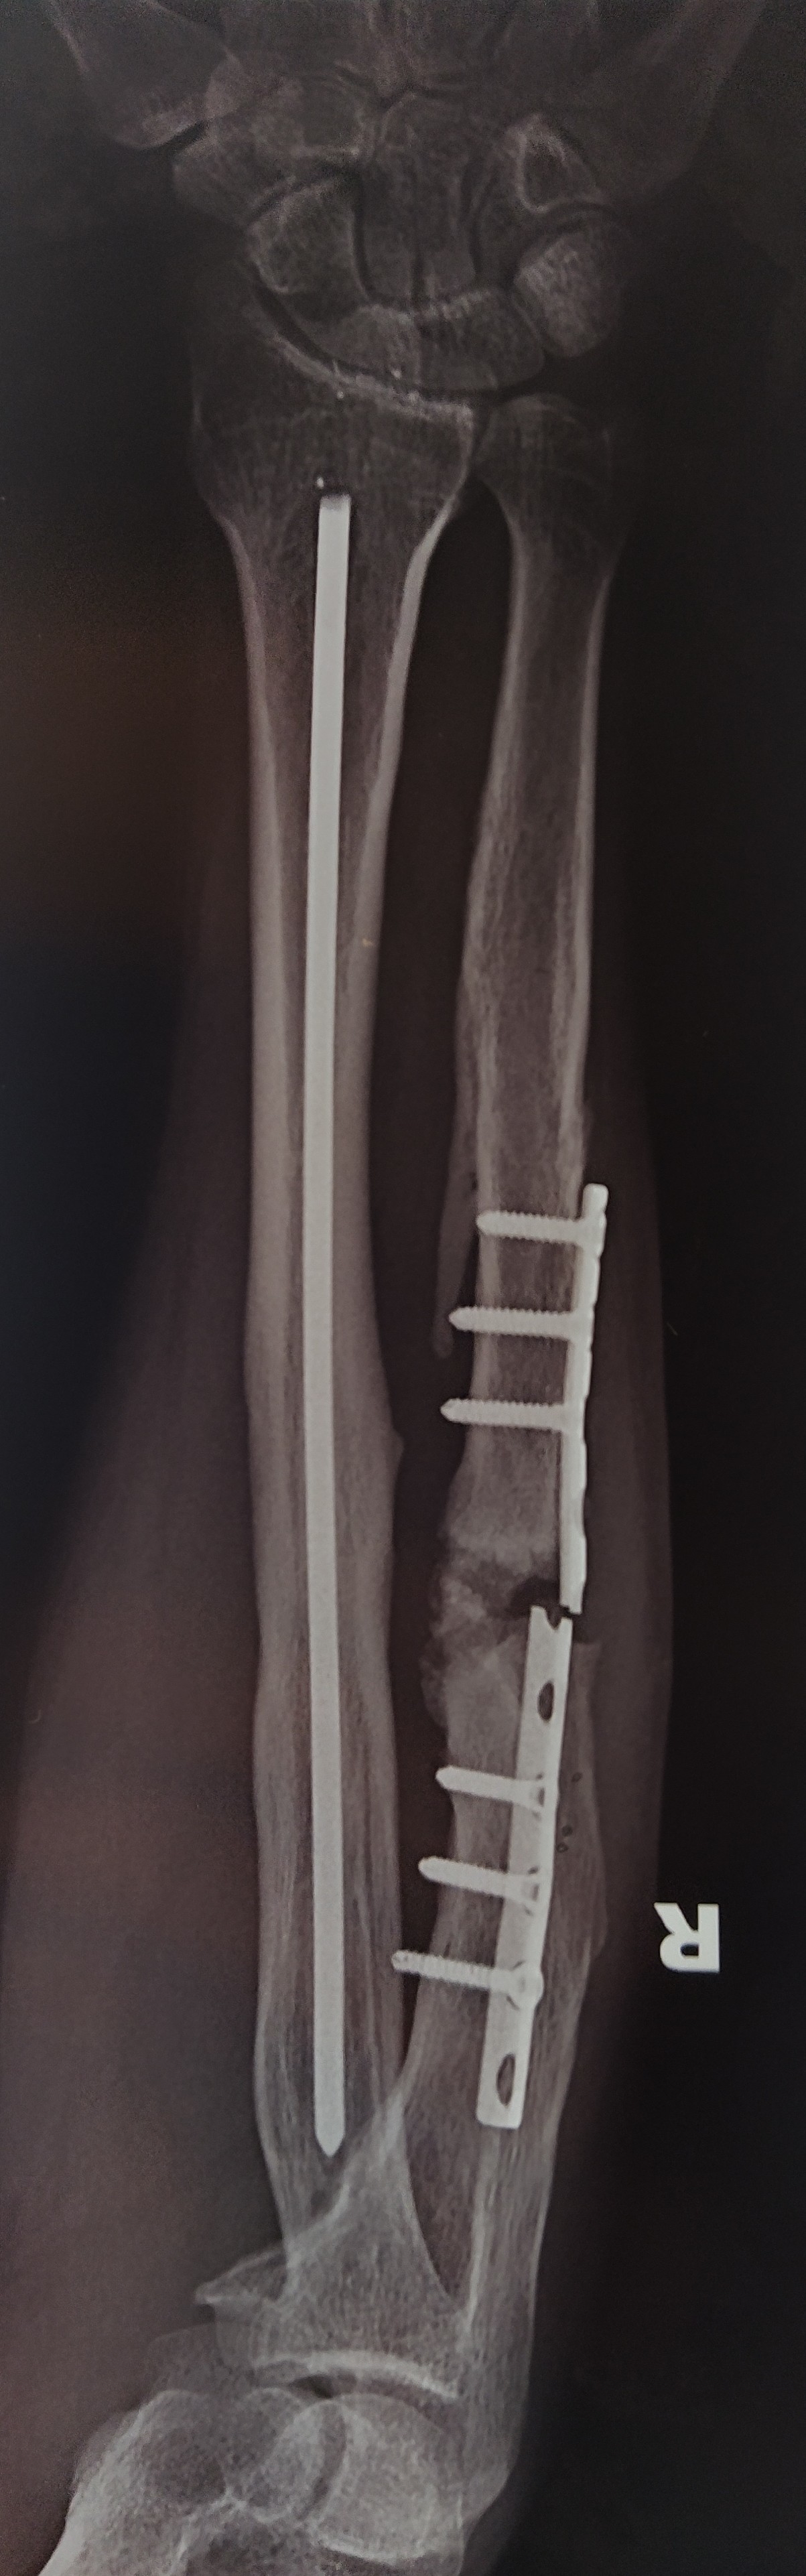

Их задача была вытащить штырь и поставить новую титановую пластину.

После операции подошёл мой лечащий врач и сказал , что спицу они не смогли вытащить и она осталось навсегда. Ну как можно конечно, но это заново ломать кость☹️

После приезда домой наблюдался 3 месяца в местной поликлиники у хирурга и меня выписали. Пошел на работу, но летом заболела рука и почувствовал что опять хрустит рука,ну всё сломалась пластина подумал! И вот итог пластина сломана рука не срослась.

А это уже 7@я операция на руку была и врач сказал "Чем больше мы туда вмешиваемся тем хуже для тебя"